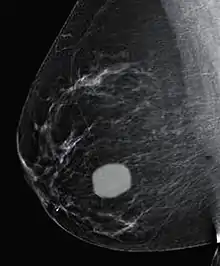

Діагностична мамограма

Мамографія використовує рентген для оцінки підозрілих мас у жінок старше 35 років. Фіброаденома на мамограмі виявляється як відмінна область від інших тканин молочної залози, з гладкими круглими краями. Фіброаденоми у літніх людей, як правило, у постменопаузі можуть містити кальцифікацію, що часто спричиняє класичний вигляд грубого попкорну. [1]

Фіброаденома, ультразвукова діагностика